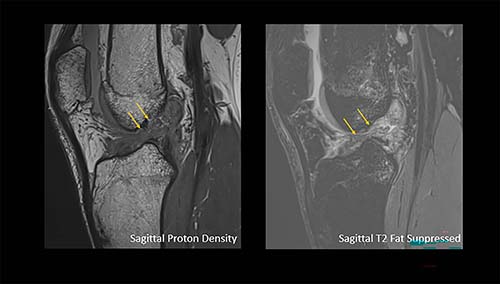

Arrows show a complete anterior cruciate ligament rupture in an 18-year-old male who had a knee injury while playing football.